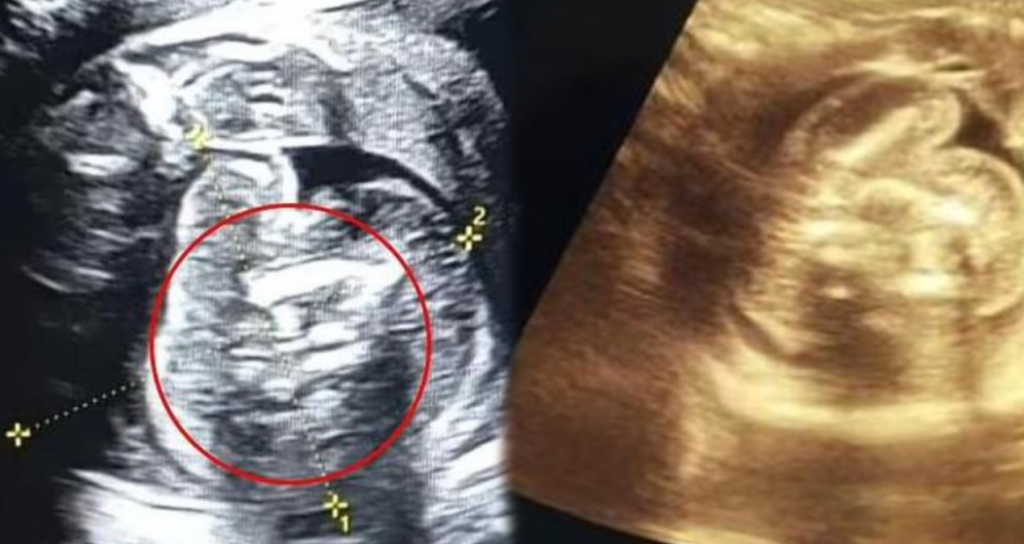

25 Haftuk Hamilelivi Sonrasi Rutin Tarama Için Mahallî Bir Hastaneyi Ziyaret Eden Bayan Domamayay Bebevin Varninda Tabipler, ‘Kemik Içeren Ek bir bir kapı’ Keşfedildi. Yapalan Tetikler Sonucunda Fetusun Karninda 2 Tane Daha Hal Bozuklağu İlku Ortaya Çikti.

Taramayı gerçekleştiren Dr. Prasad Agarwal yaşanılan durumla ilgili, “Bu bebekte çok sıra dışı bir şey fark edecek kadar şanslı ve dikkatliydim. Birkaç kemiği ve karnında fetüs gibisi bir yapı bulunan, son Derece Oloğuyen Buyen Bir Fetus.

Yahananain Oloğdayinaka Aktaran Doktor, “Bu, Dunyadaki en az Oladardady Olan ‘Fetus Isiinde Fetus’.” DUYE KONAHTU.

BU DURUMA TAM OLAK NEYIN SEBEMLEYKUNU BILMEDIKLERINI BELIRTEN Dr. Prasad Agarwal, Genellikle Erdaş Ikizler Olarak Rahim Imakinde Gelhim Sirasezda Meydana Gelürini Öne Sürür.

İKizlerin, Bir spermin bir Yumurtayi Döllemesi ve Daha Sonra Bu Yumurtanın Iki Daşka Embyoya Bölmesiyle Meydana Gelir. Hekimler, Fetüs Içinde Fetüsler Durumunda Yumurtanin Tam Oltarak Ayirmadın. Daha Sonra Ikizlerden Biri Oburunun Isiinde Silayip Kayiyor ve Tirnak, Sac VE UZUVE ÖZELLIKLER Gelish -Mertrirmaryey Devam Edebiliyor.

YUMURTA 3’E BUKUUYOR

Bu Durumda Bayandana Yumurtasi Muhtalimelen üça bökülak ayirmamaş, bunun Sonucunda Birs Canli fetürs ve iKi Fetüks olushustur. Yahanalan bu Kimekte Ise fetustiki İki Fetusun de elleri ve ayaklanlar jelihmih. AMA Fetuslerin Parazitik Otarak Kabil EDILDIYI VE HAYATTA KALMAK ISIIN HAYATI ORGANARA SAHIP DOLILLERDIR. Bu Fetusler Bazen Bebebin Aszinda, Skrotumuna, Kuyruk Sokumunda Yahut Benninde de Bulunabiliyor.